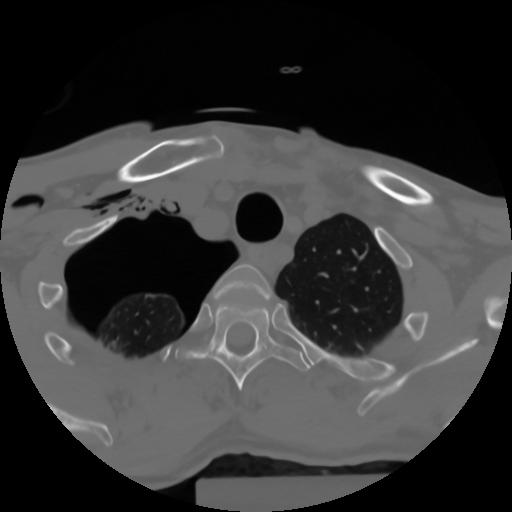

10 P.BLANDAS,,Axial,2.0,P.BLANDAS,,